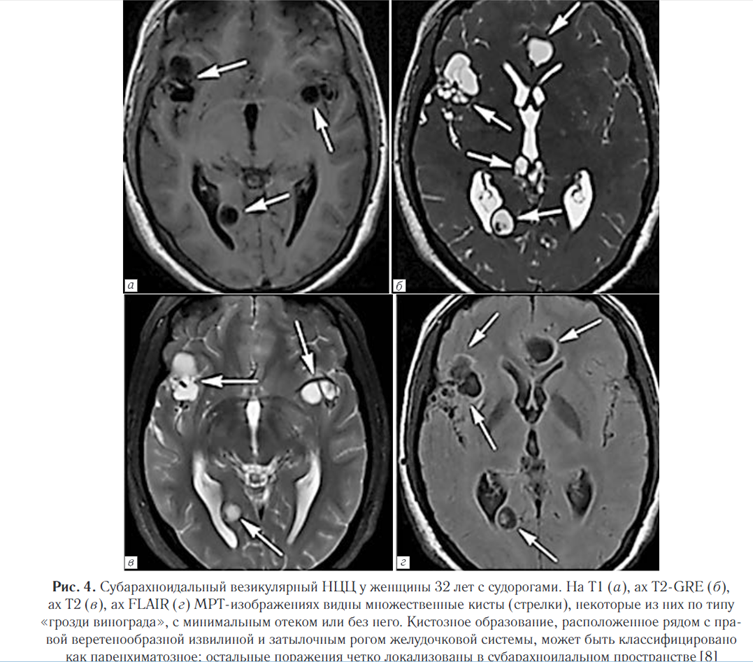

Наиболее часто изменения выявляются в IV желудочке (50%), в боковых желудочках (35%), реже в III желудочке (10%) и в водопроводе (5%). При этом изолированный желудочковый НЦЦ (т.е. без вовлечения субарахноидального пространства) отмечается в трети случаев. Свободно плавающие в желудочках цисты вызывают синдром Brunsa, это состояние характеризуется интермиттирующей обструкцией желудочкового отверстия, приводящей к периодическим головным болям, головокружениям, преходящей атаксии и редко к синкопальным состояниям; интермиттирующая обструкция IV желудочка кистами с формированием арахноидита может имитировать феохромоцитому. Интравентрикулярные кисты вызывают гранулярный эпидидимит, который может сочетаться с гидроцефалией и прогрессирующей дисфункцией среднего мозга (рис. 5) [8].